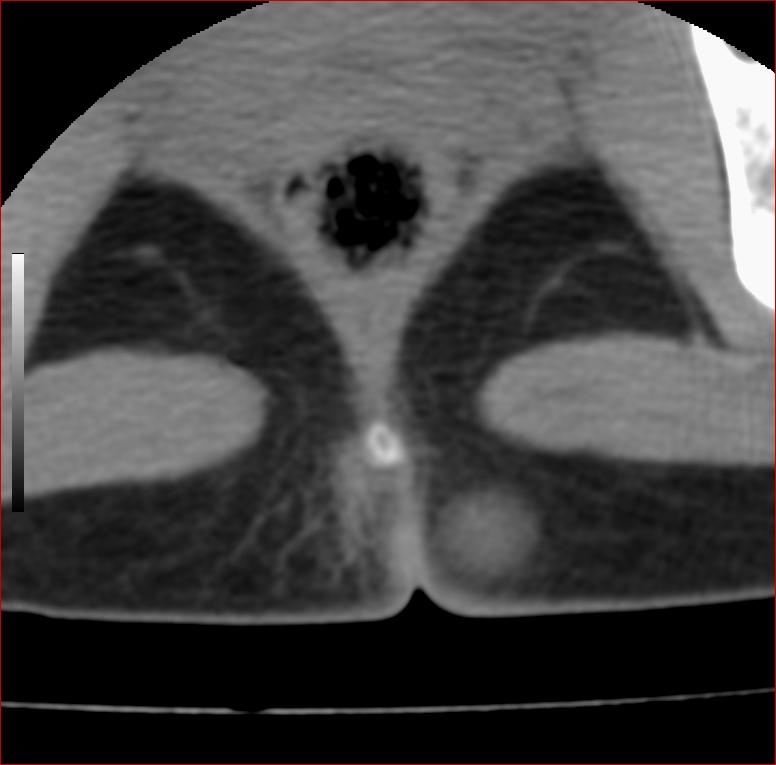

以下是引用13081830109在2007-5-16 18:51:00的发言:[br]良性病变[br]1.皮下皮脂腺囊肿[br]2.纤维瘤[br] 手术切掉就可以了

以下是引用zhangzhongshou在2007-5-16 18:21:00的发言:[br]皮下囊肿可能性大

以下是引用一个人在2007-5-16 20:35:00的发言:[br]1.皮下皮脂腺囊肿[br]2.纤维瘤[br]

以下是引用xulianj在2007-5-16 22:03:00的发言:[br]1皮下皮脂腺囊肿[br]2纤维瘤[br]3还需要除外发育畸形,如脊膜膨出。